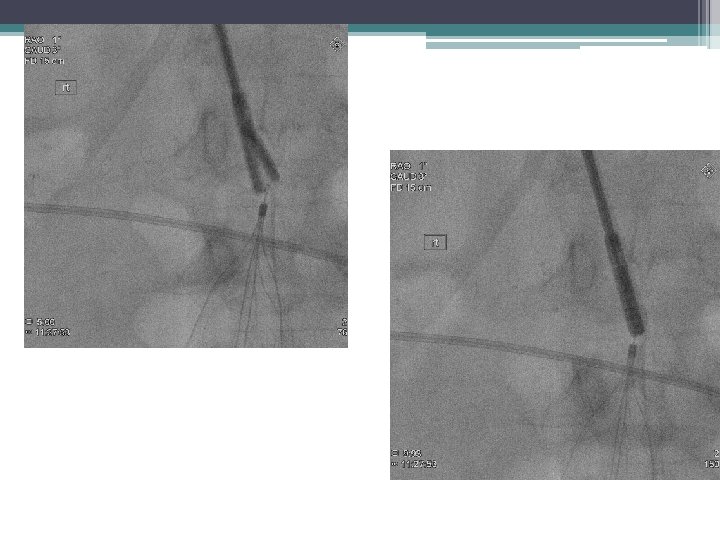

Retrieval Technique Standard • Snare • Large sheath Complex • Filter Specific • Can be adapted to retrieve permanent filters

Embedded • • Pass nitinol wire around apex snare Pass wire Balloon inflate Endobronchial forceps Excimer Laser

Migrate Tilt 11/2012 12/2012

Tilt

Excimer laser-assisted removal 98% success rate in filter retrieval, also reduced force required to retrieve filter (mean implantation time 2 -3 years; range 1 month to 18 years Kuo, W. T. , Odegaard, J. I. , Rosenberg, J. K. & Hofmann, L. V. Excimer Laser–Assisted Removal of Embedded Inferior Vena Cava Filters A Single-Center Prospective Study. Circ Cardiovasc Interv 6, 560– 566 (2013).

Excimer Laser–Assisted Removal Kuo, W. T. , Odegaard, J. I. , Rosenberg, J. K. & Hofmann, L. V. Excimer Laser–Assisted Removal of Embedded Inferior Vena Cava Filters A Single-Center Prospective Study. Circ Cardiovasc Interv 6, 560– 566 (2013). Figure used with permission.